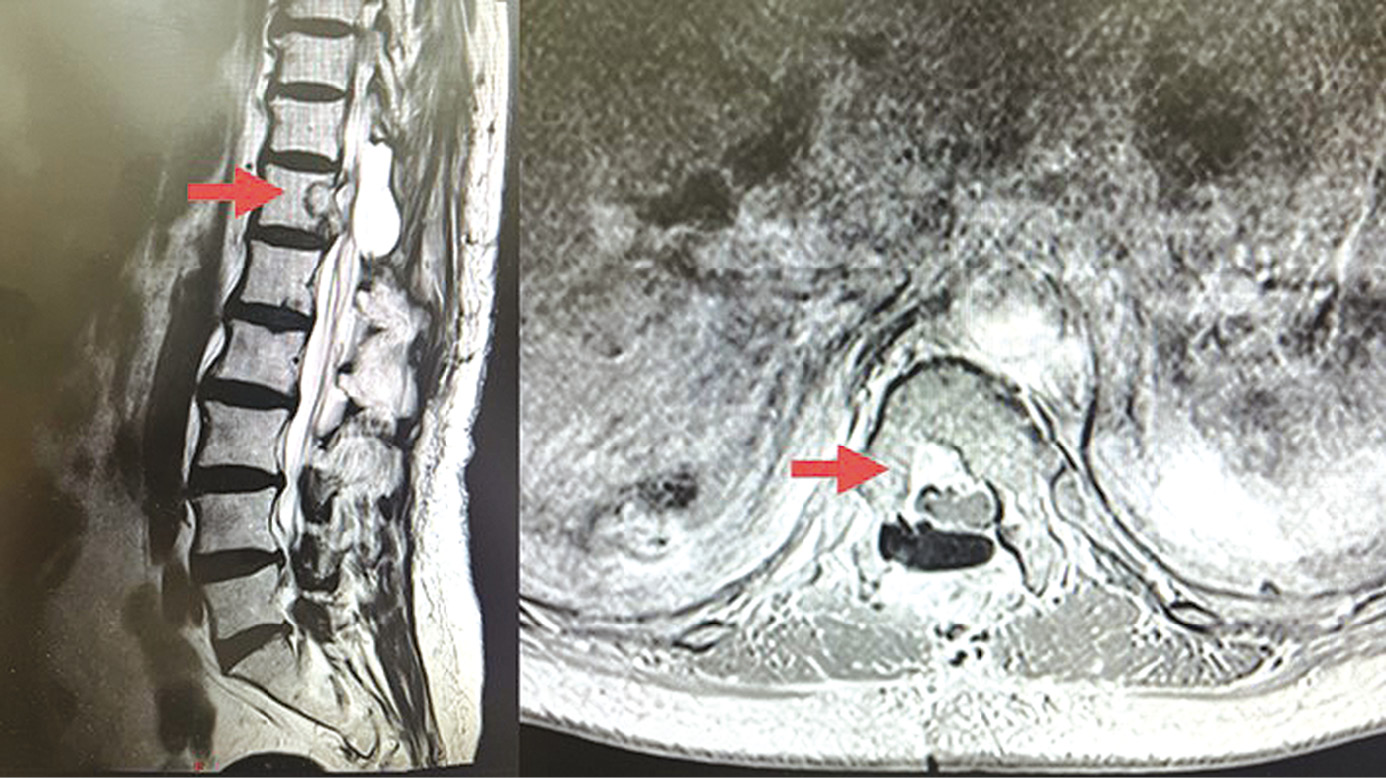

A follow-up MRI in September 2023 (5 months after SRT) revealed a tumor measuring 1.5×1.2 cm in the central parts and along the dorsal surface of the Th12 vertebral body, partially extending to the spinal canal, with moderate compression of adjacent areas of the dural sac and its contents (Fig. 4). The patient reported a decrease in right side back pain and pain in the right leg (pain intensity on a visual analogue scale: 50%–60%). There were no sleep disorders; the dose of tramadol was reduced to 500–100 mg/day (1–2 tablets). The patient was able to walk without the assistance of family members.

A follow-up MRI in May 2024 (13 months after SRT) revealed a tumor measuring 1.3×1.0 cm (previously 1.5×1.2 cm) along the posterior surface of the Th12 vertebral body, extending to the spinal canal, with diffuse, heterogeneous contrast uptake and moderate compression of the dural sac. There were no signs of local recurrence and/or disease progression; the clinical condition was stable (Fig. 4).

Fig. 4. MRI of the spine, T1 mode. The top photo is 5 months after stereotactic radiation therapy (stabilization). The lower photo is 13 months after stereotactic radiation therapy, T1 mode (stabilization).

Рис. 4. МРТ позвоночника, режим T1. Верхнее фото — через 5 мес. после стереотаксической лучевой терапии (стабилизация). Нижнее фото — через 13 мес. после стереотаксической лучевой терапии, режим T1 (стабилизация).